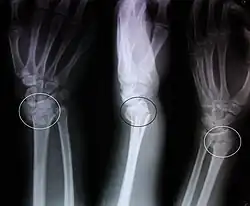

![]() Imagen radiográfica anteroposterior y lateromedial de una fractura de Colles | ||

La fractura de Colles es una fractura distal del radio. La fractura se reconoce clínicamente por la deformidad en "dorso de tenedor" debido al desplazamiento dorsal del fragmento distal del radio. Para una discusión más detallada, ver la fractura distal del radio.

Hallazgos radiológicos típicos

- Inclinación dorsal y radial de la muñeca.

- Acortamiento radial.

- Desplazamiento dorsal del fragmento distal.

- A menudo asociada a fractura del apófisis estiloide cubital.

- Ángulo volar < 10°.